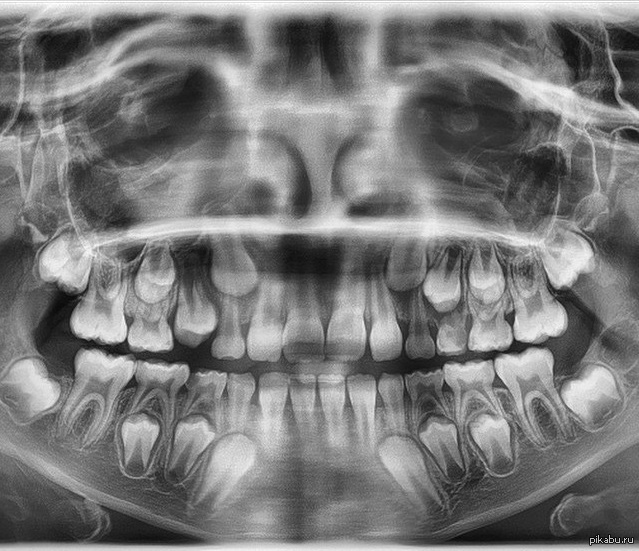

Фотографии ортопантомограмм и работ Родена